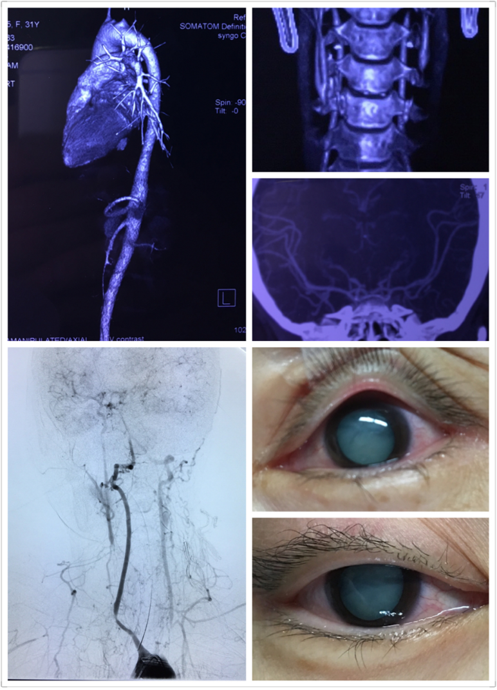

背景1:有些患者并不能等待至炎症静止期,临床中曾遇到这样一个真实病例:一位刚结婚的年轻女性,因头痛、眩晕、视力模糊就诊,确诊为头臂型TAK并处于活动期。按照常规流程,她被转至风湿免疫科进行抗炎治疗。然而,就在等待炎症控制的短短数日内,患者突发脑卒中。

这个悲剧性的案例抛出了一个尖锐的临床问题:对于那些不能等待、或者在内科治疗期间仍出现缺血症状的患者,我们是否必须死守“静止期”才能手术?